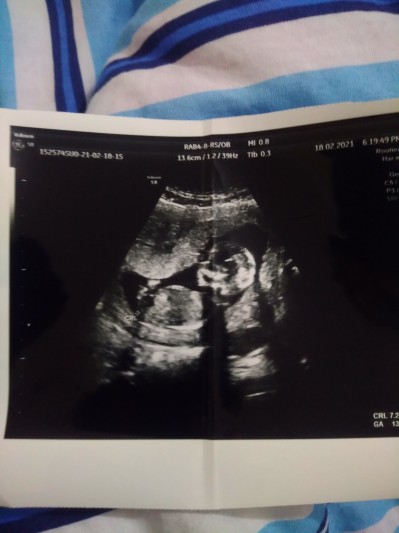

Biz özel hastaneye gidiyoruz. 12 haftalıkken kesin olmadan öğrenmek istemememe rağmen doktorumuz cinsiyetini kız dedi. 1 hafta sonra gel netleştirelim dedi. 13 haftalıkken erkek dedi. Bacak arasında hafif çıkıntı var. Ama bu sefer de kesin gibi konuşmadı. Araştırıyorum erkek denip kız çıkan da var kız denip erkek çıkanda. Bacak arasında çıkıntı olduğu halde yanılma payı olabilir mi? Klitoris ya da dudaklarla karıştırılabilir deniyor. 13 haftalık net cinsiyet için erken diye düşünüyorum. Sizce ayrıntılı ultrasonu mu beklesem, yoksa başka doktora mı gitsem?

Gebelik haftası 14

Ben nettende çok baktım erkek bebek ultrason resimleride hep buna benziyor

Erkeğe benziyor ama böyle olunca kordonlada karistiralabiliyor 16 .haftani bekle bakalım canım ozman belli olur

13.haftada aynı babada böyle bi resim verip erkek dedi.yüzde 5 yanılma olur dedi. Ama pazartesi kontrol var belki daha net belli olur

Netlesince yazmamı istemiştiniz. Bugün Dr kontrolüm vardı ve cinsiyeti değişmedi yukardaki gibi bir görüntü gösterip erkek dedi. Sanırım erkek denilince pekte değişmiyor.

buda benim bebeğimin görüntüsü 13 +3 gunlukkken banaa da erkeğe benziyor dedi bende meraktayim ama senin sanki daha net erkek olduğu canım haayirlisiyla kucağımiza alalım da inşallah bana da benim kız gibi geliyor hep